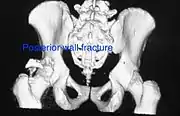

Posterior wall fracture as seen on 3-D CT scan

| Posterior wall | This is the most common variety of acetabular fracture. It typically occurs due to dashboard injury; when a person travelling in a vehicle involved in a head-on collision, the force applied over the flexed knee travels along the femur bone to the head of the femur, breaking the posterior wall of the acetabulum. The head of the femur is dislocated outside the joint. | T shape | When a transverse fracture also had a vertical fracture line, it is called a T shape fracture. Here the innominate bone is broken in such a way that all three parts of it, the ilium, the ischium and the pubis are separated from one another. This is a three part fracture. Though both columns are broken, the weight bearing dome is still attached to the main part of the ilium and hence it is not a true fracture of both columns.

- Posterior wall fracture: Iliac oblique and obturator oblique views